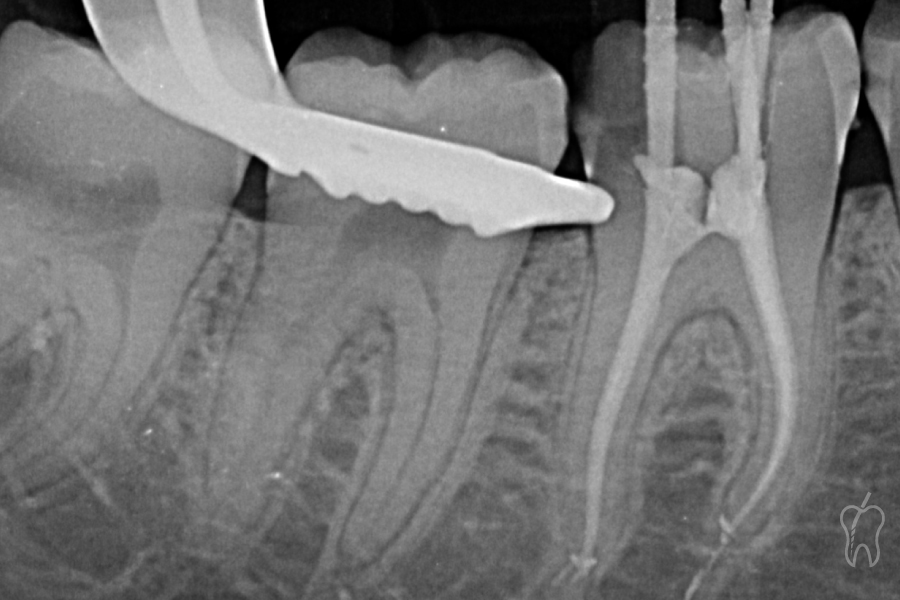

Una vez completada la irrigación y secado del sistema con puntas de papel calibradas, se procedió a la obturación mediante técnica termoplástica utilizando obturadores con transportador de vástago plástico (Endogal, Sarria, España) (Figura 5). Esta técnica permite una condensación tridimensional del material, adaptándose a irregularidades, istmos y zonas de confluencia del sistema radicular.

Como sellador se empleó EndoResin (Endogal), un cemento de resina con alta fluidez y estabilidad dimensional.

Figura 5

Con la cámara pulpar completamente limpia y manteniendo intacto el puente dentirario generado por el acceso tipo Truss, se procedió a la fase restauradora.

En primer lugar, se colocó una matriz Palodent (Dentsply Sirona) en la zona distal, junto con cuña y anillo, para recuperar correctamente el contorno proximal y garantizar un sellado adecuado en una zona de difícil acceso debido a la caries previa (Figura 6)

Desde ese acceso distal, se aplicó SDR (Denstply Sirona), permitiendo que el material fluyera por debajo del puente dentinario y alcanzara la zona mesial (Figura 7). Esta maniobra permitió:

• Sellar de forma eficaz las áreas más profundas e inaccesibles del tercio coronal.

• Reforzar la base interna.

• Mantener la integridad del puente dentinario sin necesidad de retirarlo.

Figura 6

Figura 7